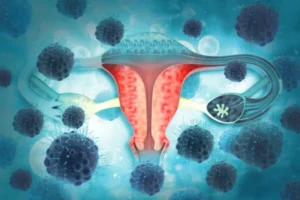

سرطان عنق الرحم هو مجموعة الخلايا التي تبدأ النمو في عنق الرحم. وعنق الرحم هو الجزء المنخفض من رحم المرأة الذي يتصل بالمهبل. تؤدي سلالات

سرطان المِبيَض هو نمو للخلايا المتكونة في المِبيَضين. تتضاعف هذه الخلايا سريعًا ويمكن أن تغزو أنسجة الجسم السليمة وتدمرها. يحتوي الجهاز التناسلي الأنثوي على مِبيضين،

لأورام الليفية الرحمية أورام شائعة تتكوّن في الرحم. وتظهر عادةً خلال السنوات التي يمكن فيها حدوث الحمل والولادة. والأورام الليفية الرحمية غير سرطانية ولا تتحول